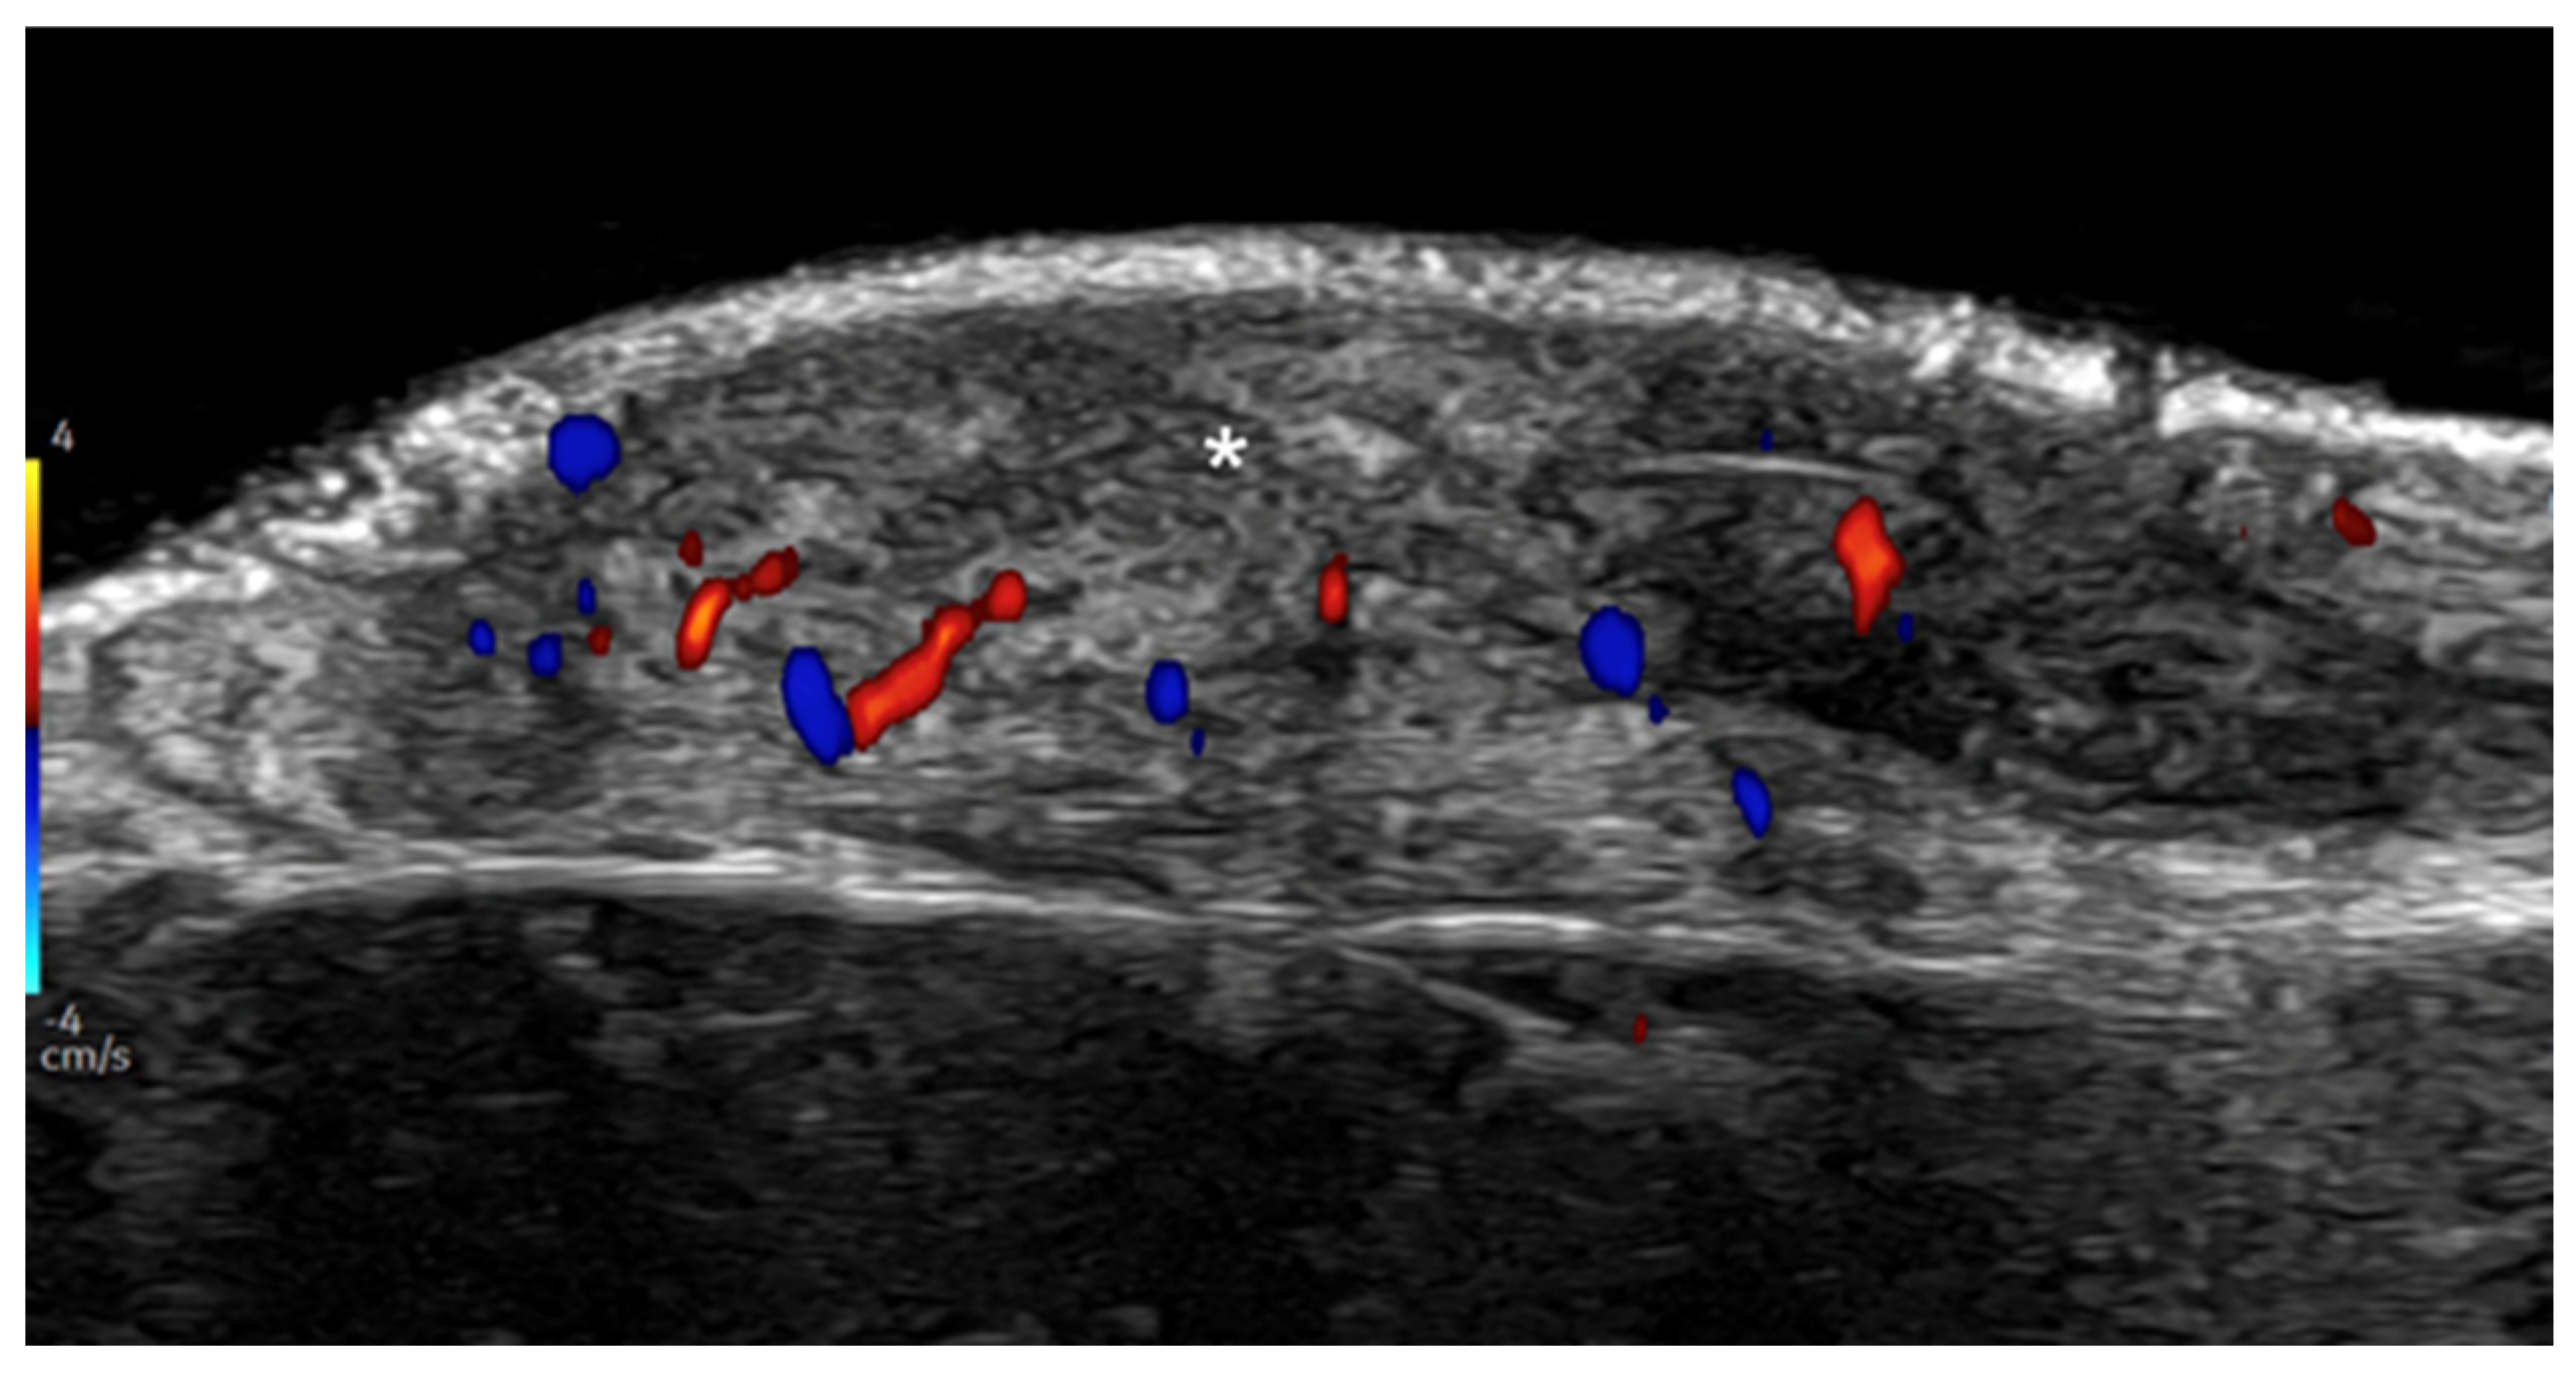

- Parra-Cares, J.; Wortsman, X.; Alfaro-Sepúlveda, D.; Mellado-Francisco, G.; Ramírez-Cornejo, C.; Vera-Kellet, C. Color Doppler Ultrasound Assessment of Subclinical Activity with Scoring of Morphea. J. Cutan. Med. Surg. 2023, 27, 454–460. [Google Scholar] [CrossRef] [PubMed]

- Wortsman, X.; Vera-Kellet, C. Ultrasound Morphea Activity Scoring (US-MAS): Modified US-MAS. J. Ultrasound Med. 2023, 42, 2447–2450. [Google Scholar] [CrossRef] [PubMed]

- Vera-Kellet, C.; Meza-Romero, R.; Moll-Manzur, C.; Ramírez-Cornejo, C.; Wortsman, X. Low effectiveness of methotrexate in the management of localised scleroderma (morphea) based on an ultrasound activity score. Eur. J. Dermatol. 2021, 31, 813–821. [Google Scholar] [CrossRef]